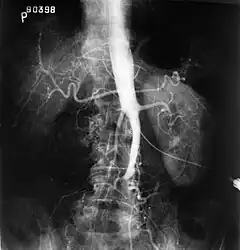

Angiography provides important information regarding the perfusion and patency of distal arteries (e.g. femoral artery). The presence of collateral arteries in the pelvic and groin area is important in maintaining crucial blood flow and lower limb viability. However, angiography should only be used if symptoms warrant surgical intervention.[8]

Plate from Gray's Anatomy showing the abdominal aorta and the common iliac arteries.

Fluoroscopic image of an affected aorta